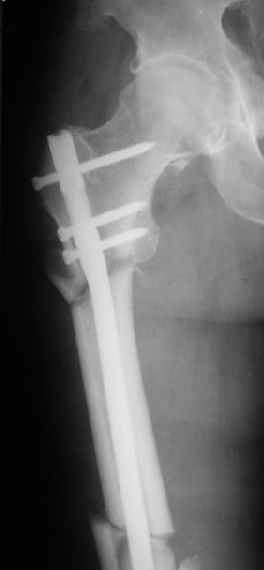

При межвертельных переломах с цефаломедуллярными гвоздями бывает, что проксимальый винт проходит или черед периферический отломок, или прямо над ним. И если остался диастаз, то этот винт при осевой нагрузке не дает сблизиться отломкам. Пример такого остеосинтеза в застарелом случае в приложении.

В качестве предупреждающей меры можно долотом разрушить латеральную стенку дистального отломка под винтом.

В частности, на проксимальном конце сделано еще одно дополнительное статическое отверстие. Можно ввести в проксимальном отделе 4 винта, из них 3 статические (2 в круглые отверстия и 1 по нижнему краю овального). Картинки в приложении. На дистальном конце стержня тоже кое-что улучшено. Спрашивайте в аптеках, как говорится. Выпускается предприятием "ЦИТО" (Москва), то есть это малобюджетное решение.

Конечно, мы не синтезируем остеопорозые вертельные переломы согласно прилагаемому примеру, винты 6 мм вырежутся. Но у более молодых при хорошем качестве кости такие или подобные гвозди с поперечным расположением винтов вполне применимы для меж- и подвертельных переломов.

Это было года 2,5 назад, мы тогда еще уточняли возможности шинирования с угловой стабильностью гвоздем с поперечным расположением винтов при переломах проксимального отдела бедра. Пациенту не пришлось приобретать намного более дорогой рекон или проксимальный гвоздь. В приложении еще несколько примеров применения того гвоздя при высоких переломах бедра, в том числе с более латеральной точкой входа. Гвоздь изгибаем для этого.